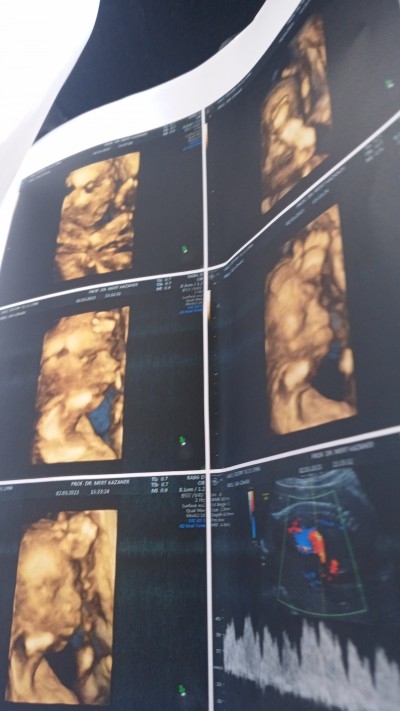

2 Mart 2023 Hamilelik Dönemi Genel kategorisinde (31 puan) sordu

Artık cinsiyet degsmez demi 20 haftalk oldum ayrintilida  kız dediler sizce alışveriş yapmaya baslaym.mi

image.